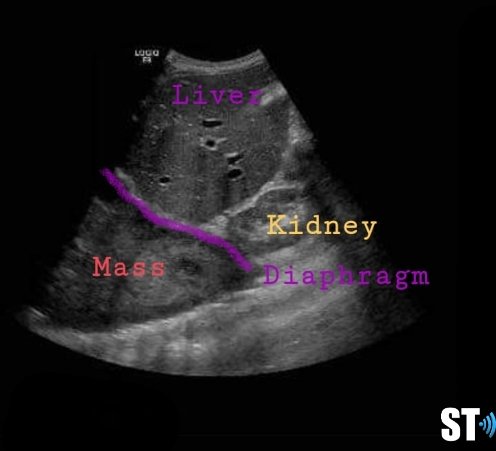

Right sided hernia with liver and hypoplastic lung

Liver and gallbladder in right chest